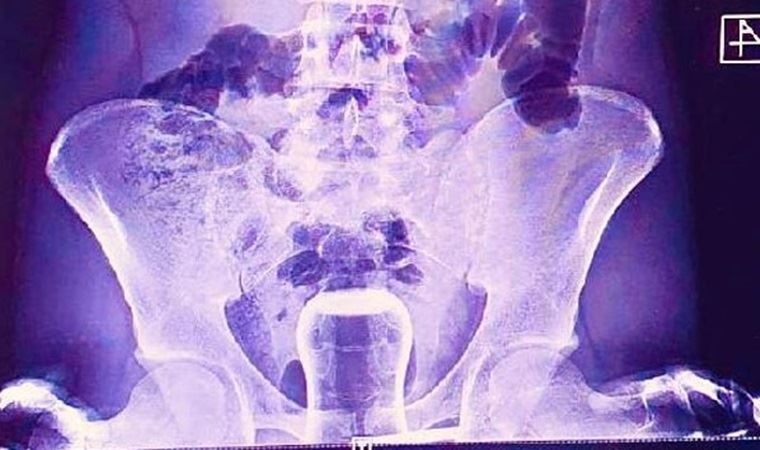

Şanlıurfa’da basur hastası olan bir kişinin iddiaya göre tedavi için hacamat yaptırırken yağlı çay bardağı anüs bölgesine kaçtı. Bardak ameliyatla çıkarıldı. Bu haber ve ona eşlik eden röntgen filmi görüntüsü dün gün boyu sosyal medyanın başlıca geyik konusuydu.